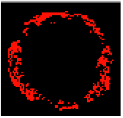

Previous studies have identified texture analysis as being useful in the analysis of ultrasound images. Plaque components appear with different texture patterns in IVUS images (Figure 11). Therefore, texture analysis methods are best suited to classifying pixels from plaque areas of IVUS images into three tissue classes, including dense calcium (DC), necrotic core (NC), and fibro-fatty (FF) [47].

Figure 11.

Different tissue types in the plaque area of IVUS images: (a) dense calcium, (b) necrotic core, and (c) fibro-fatty.